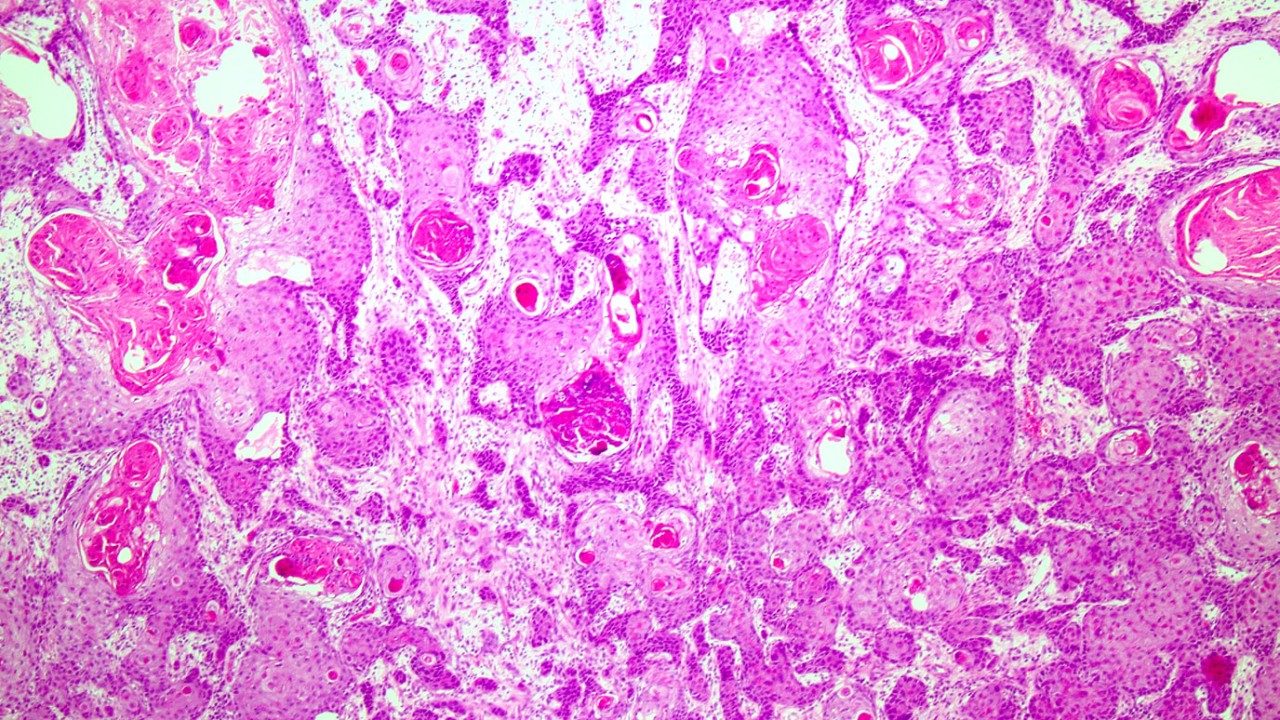

Squamous cell carcinomas: 8 things to know about the ‘cancer of the surfaces’

Much like adenocarcinomas, squamous cell carcinomas can develop in many locations, including the skin, lungs and cervix.

Unlike...